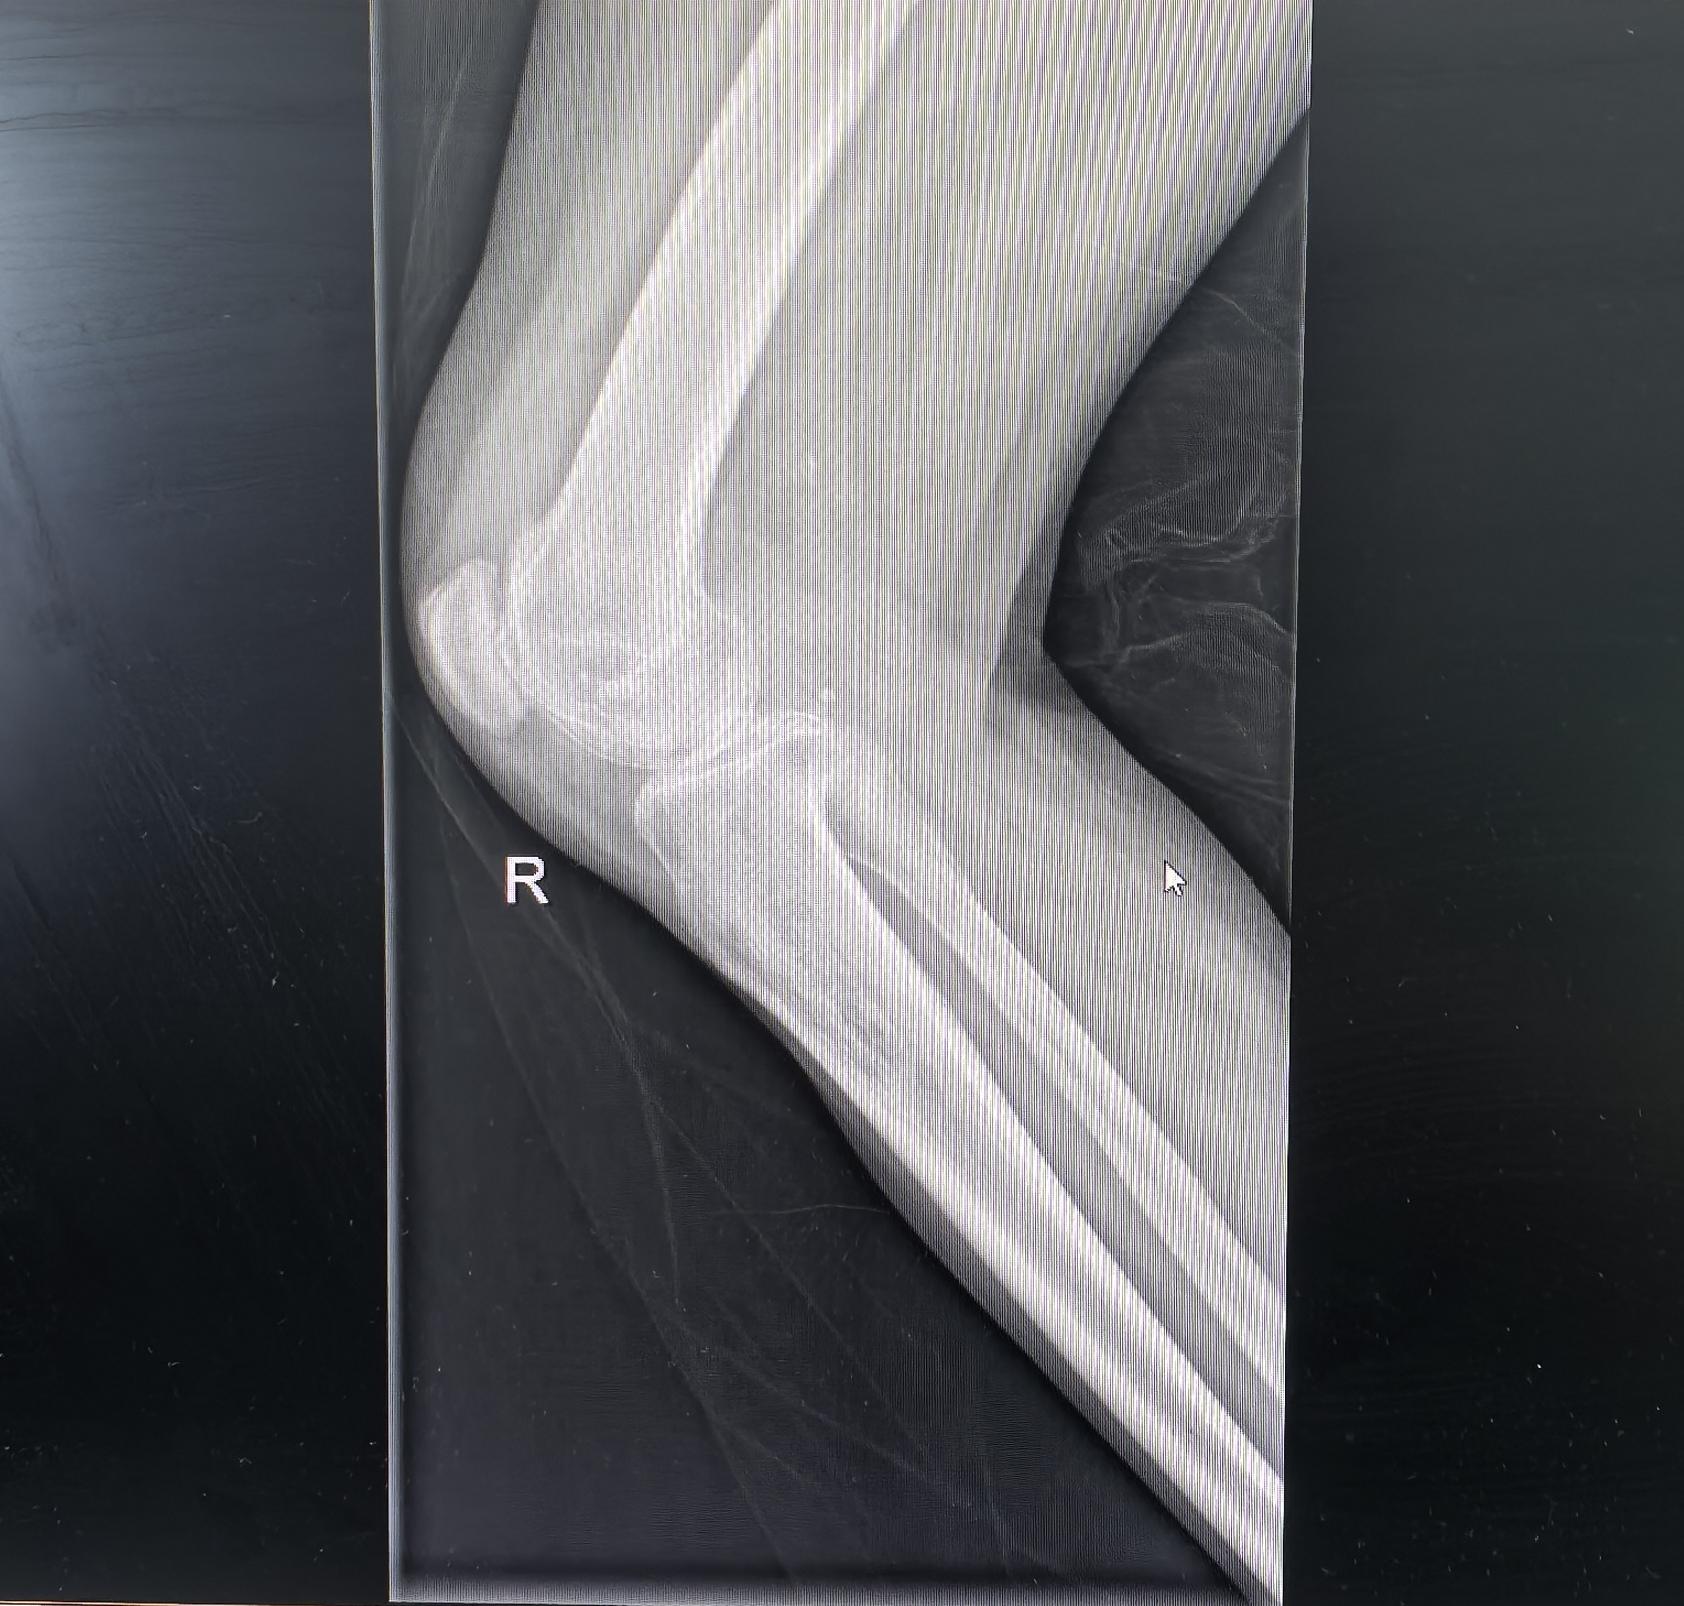

膝关节置换,类风湿关节炎。类风湿关节炎,屈曲挛缩合并外翻畸形